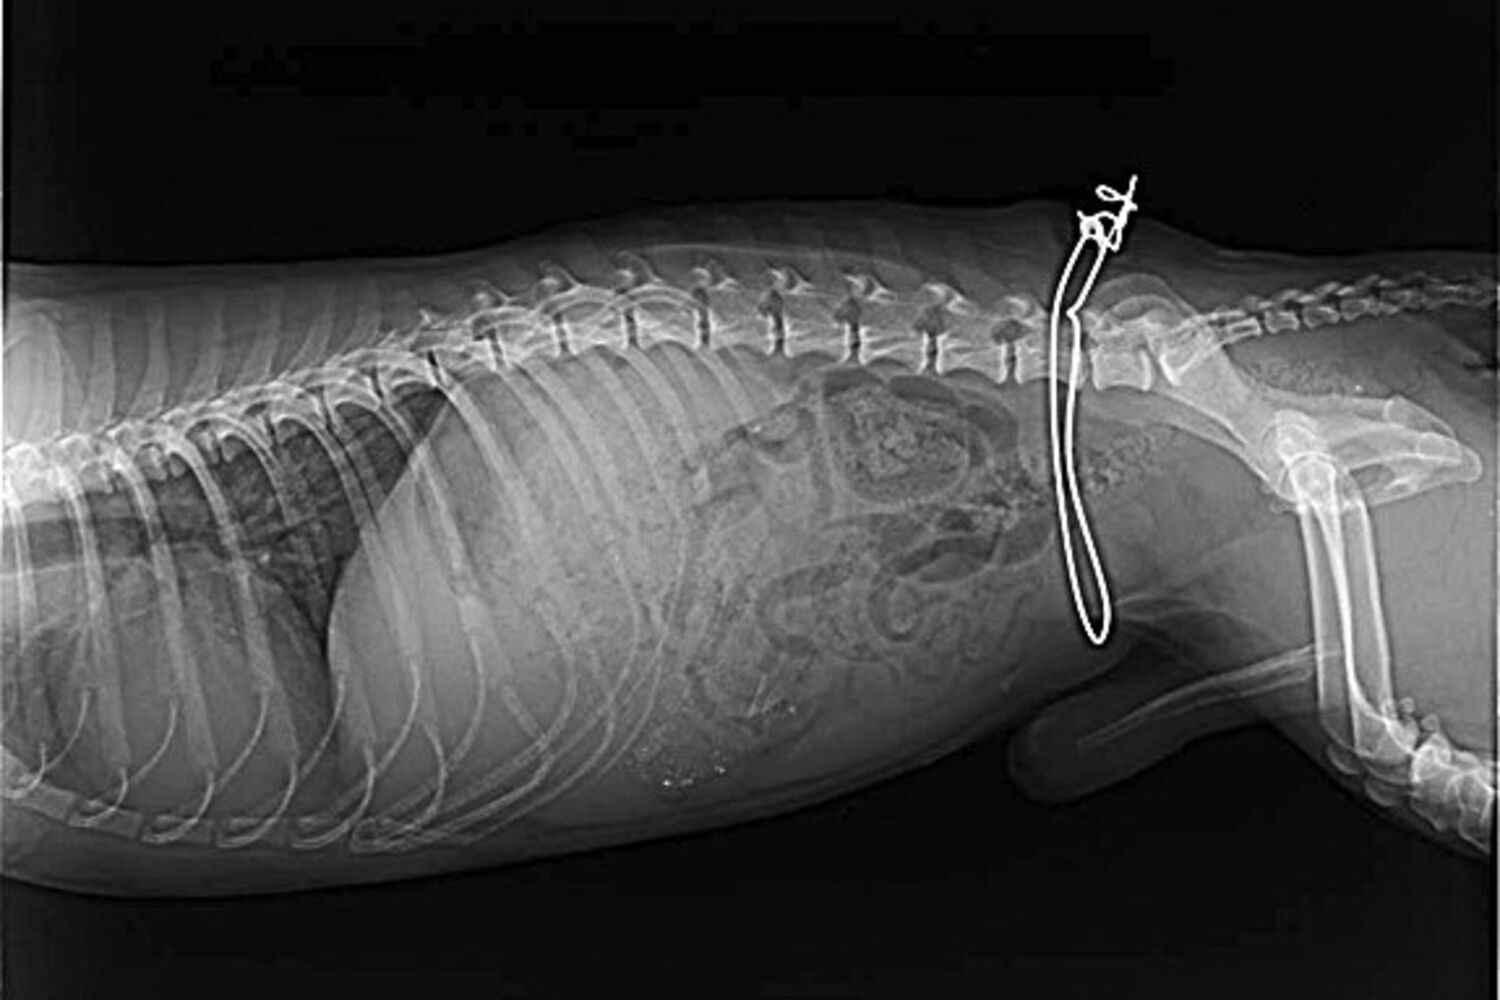

Arame, que ficou preso ao animal, já estava coberto pela pele.

A ADAPO - Associação de Defesa dos Animais e Plantas de Olhão recolheu um cão com uma armadilha de caça artesanal à volta do corpo, já no interior da pele. O animal tinha sido apanhado, há mais de um mês, na zona de Olhão, e como o arame do dispositivo ficou preso, começou a ser absorvido pelo corpo do animal. O cão já foi operado, com sucesso, e espera agora por uma casa de acolhimento.

"As voluntárias foram ao terreno e tiveram muitas dificuldades em recolher o cão, que estava muito medroso e agressivo, mas quando finalmente conseguiram, perceberam bem o grave estado em que estava", contou ao CM Célia Caravela, presidente da ADAPO. O animal não tinha conseguido libertar-se da armadilha de caça e já tinha o arame completamente envolto pela pele, que entretanto cobrira a ferida.

A cirurgia para retirar o arame foi realizada por um veterinário local e o cão, sem raça conhecida, está para adoção.